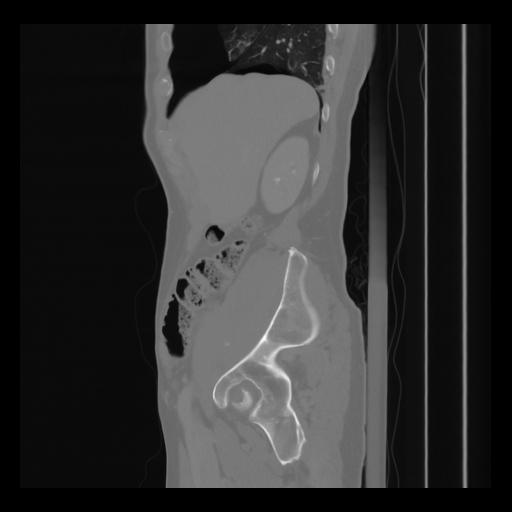

36 CUERPO,CE,Sagittal,3.000,CUERPO,Sagittal,